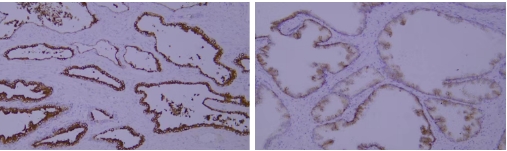

Typical example: Staining of paraffin-embedded human prostate cancer tissue sections with different PSAP antibodies:

Left panel: Strong cytoplasmic positivity in cancer cells, indicating correct cellular specificity and subcellular localization of the antibody.

Right panel: Weak membranous positivity in cancer cells, where the antibody shows correct cellular specificity but incorrect subcellular localization, suggesting inaccurate specificity.

Recommendation for Resolution: Prioritize antibodies with accurate tissue specificity, cellular specificity, and subcellular localization specificity, as this is the core principle for primary antibody selection.

Typical example: Staining of paraffin-embedded human breast cancer tissue sections with different HER2 antibodies:

Left panel: Strong membranous positivity in cancer cells;

Right panel: Weak membranous positivity in cancer cells, indicating insufficient staining intensity of the antibody.

Common problem: Insufficient staining intensity can result in weak positivity in detection results.

Recommendation for Resolution: Appropriately adjust the antibody dilution ratio, or select antibodies with high staining intensity and high affinity.